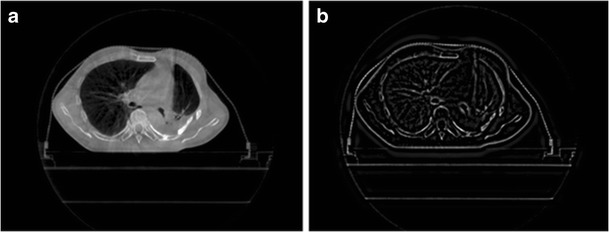

The high-frequency sub-band of wavelet transform has the ability to highlight the differences between neighboring pixels in an image [25]. Large wavelet coefficient indicates the boundary of two distinct intensity regions in the original image. Stationary wavelet transform is translationally invariant, which helps to identify the image edge features. In order to improve the resolution of edge details, image with prominent edge features can be reconstructed by using the inverse SWT with the three groups of wavelet vectors (LH, HL, HH). The CBCT image and the gradient image generated with SWT are shown in Fig. 3.

Fig. 3.

The CBCT image and the gradient image produced after the SWT. Part a is the original CBCT image and Part b is the gradient image after the SWT